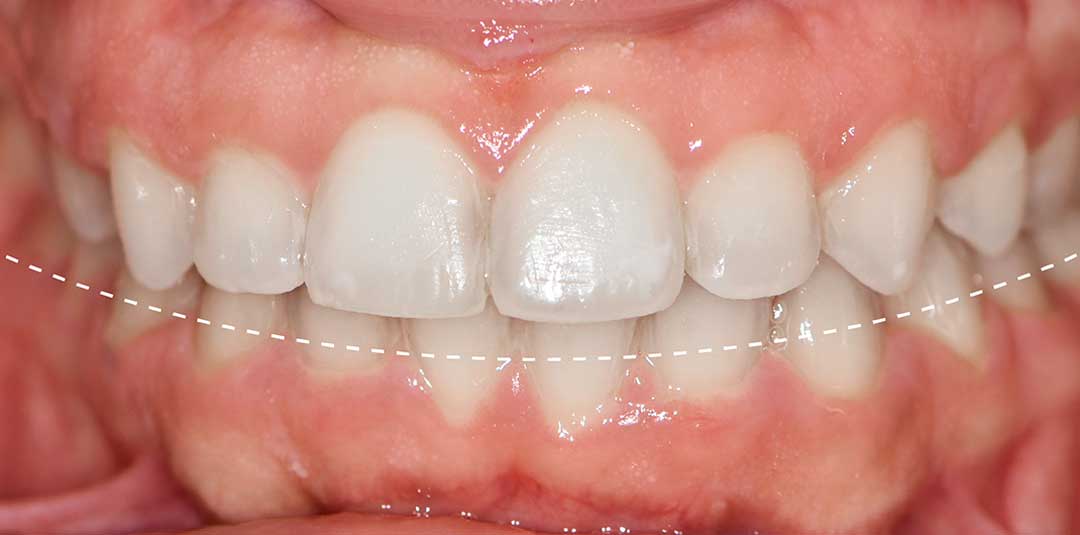

Beautiful Smiles

by Dr. Paolo Bellini